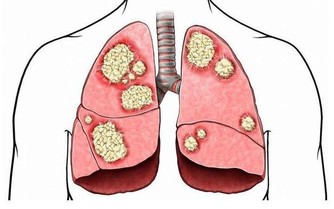

肺癌是“癌症之王”,是人類死亡的頭號殺手。肺癌的發病率男性多於女性,城市多於農村。

肺癌就像一種慢性自殺一樣侵襲著人類的健康,來的時候一聲不響,一旦發作就是肺癌晚期。因肺癌死亡的明星也不在少數,如著名喜劇小品演員趙麗蓉、帽子歌后鳳飛飛、著名演員閆懷禮等。

肺癌並非吸煙一族的專利,經常接觸二手煙、做飯的女性也是肺癌的高危人群。肺癌的致病因素比較複雜,空氣污染、環境因素、粉塵、刺激性氣味環境、遺傳史等等都是導致肺癌的致命因素,它就像一種慢性病一樣,在某種致病因素的長期刺激下,正常細胞會發生癌變,慢慢地形成腫瘤。據了解,閆懷禮在河北涿州拍攝一部叫《俏羅城》的電視劇。當地的蒼蠅、蚊子特別多,當時有一場戲拍戲的現場噴灑了很多敵敵畏,很多人都因為濃重的味道離開了,當時閆懷禮嗅覺不好感覺不到,長時間處在敵敵畏濃重的環境裡面,拍戲空擋還在那裡休息,好友六小齡童分析這是他患病的誘因之一,再加上多年拍戲工作太過勞累,閆懷禮才患上了肺癌。

肺癌幫介紹,肺癌是一種高隱藏性癌症,潛伏期最長達10年。早期沒有明顯症狀,當有的人發現腰痛、腿疼、肩痛的時候,可能肺癌已經發生了轉移,但前期沒有任何症狀。這樣的例子生活中很常見,也給我們的健康敲響了警鐘,每年定期體檢和癌症篩查是很有必要的。